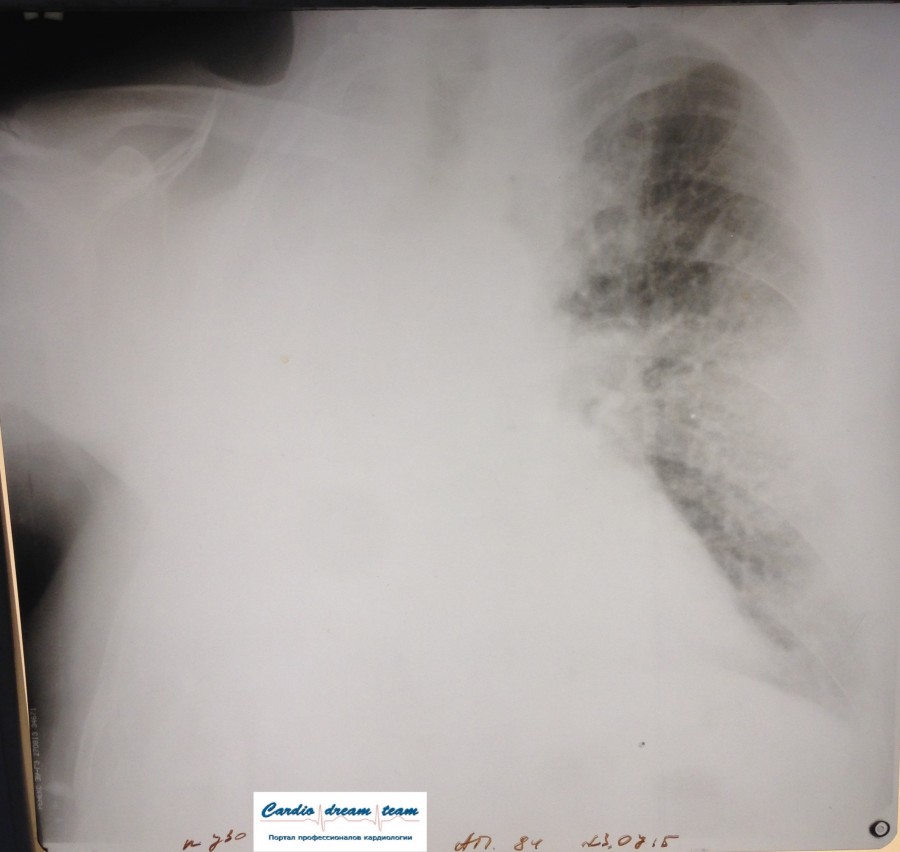

Заголовок сообщения: Одно легкое

Правое легкое удалено в 1990 году. Была онкология.

Среднедолевая пневмония. Слева легкого нет.